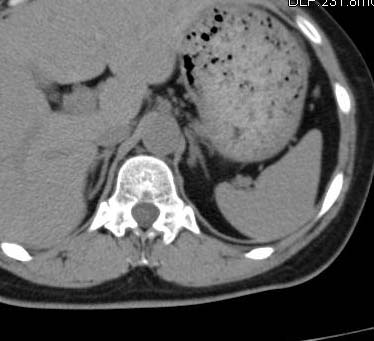

左侧肾上腺内侧肢相对增粗,(同同层面膈肌最厚处相比无明显增粗),似有一结节影,增生或小腺瘤?

左侧肾上腺内支增粗,未见确切占位征象,考虑为增生,